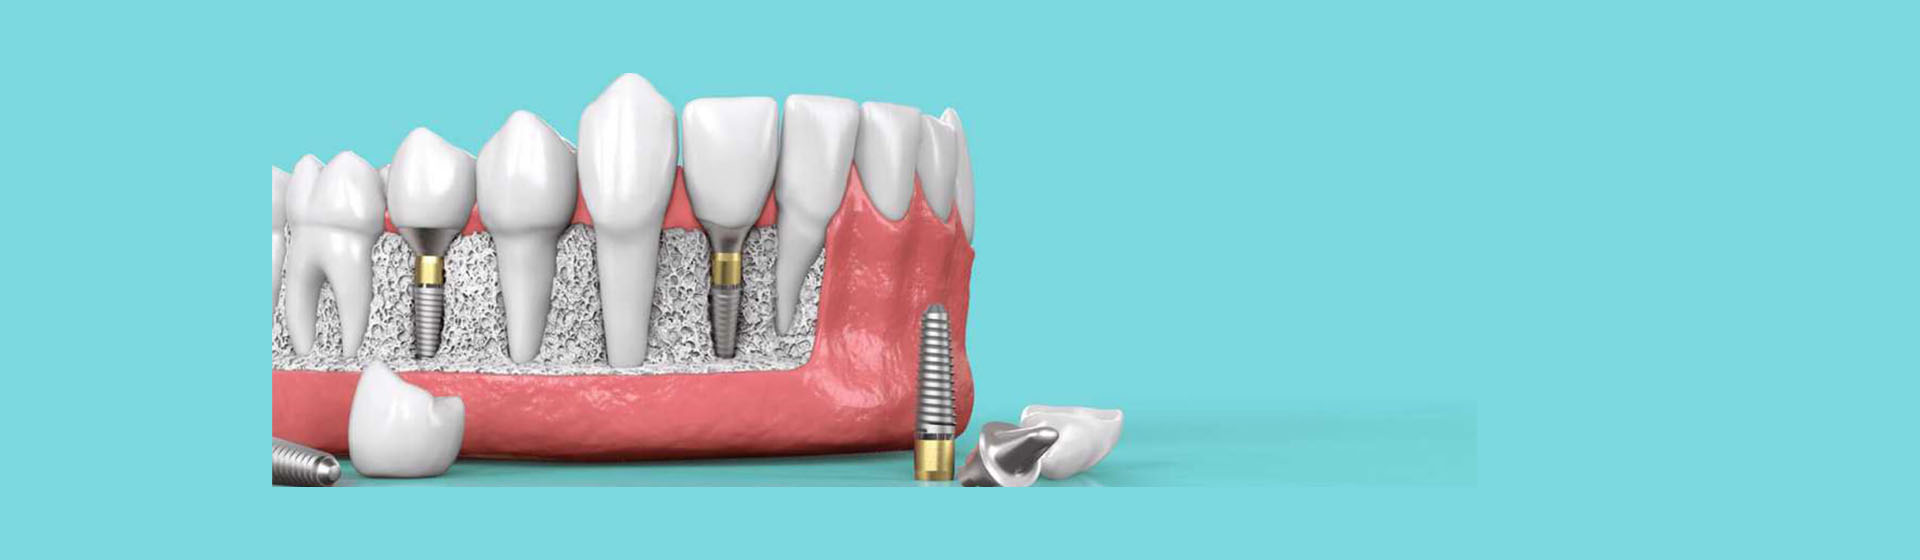

Understanding the components and benefits of dental implants

A dental implant is an artificial tooth root, usually made of titanium. A complete dental implant has three components:

A titanium root form that is surgically placed into the jawbone.

A connector, placed on top of the implant root form before a crown is secured to it.

A restoration to replace the visible, white portion of your tooth.